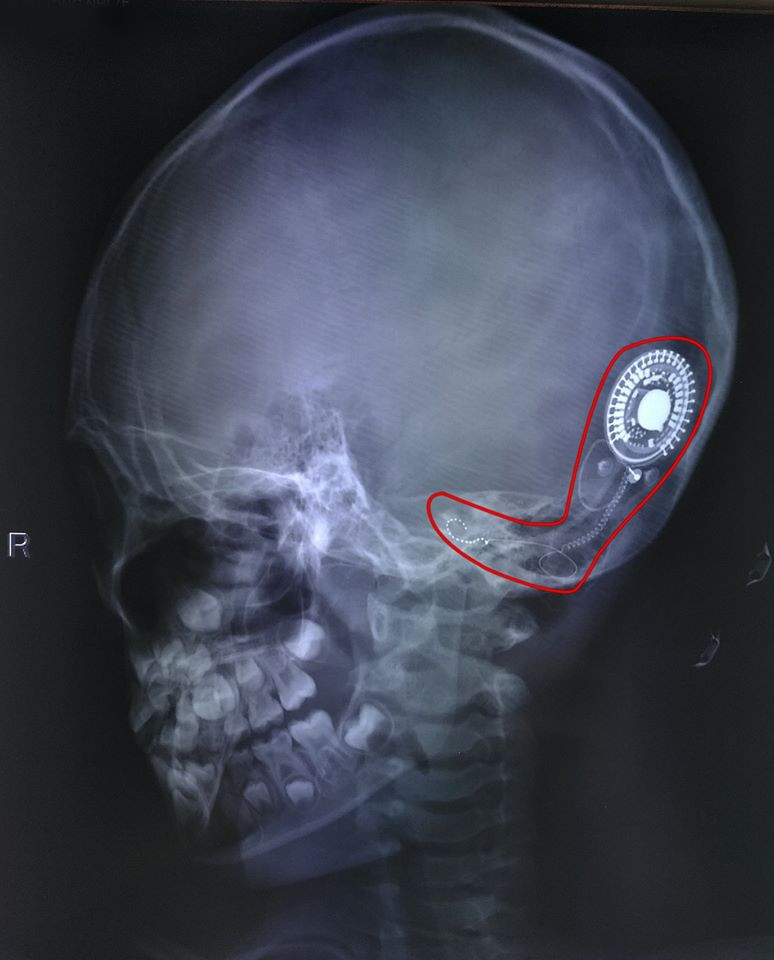

Chiếc ốc tai điện tử được gắn vào tai phải cho bệnh nhi 7 tuổi giúp thoát điếc bẩm sinh.

Đây là phương pháp phẫu thuật hiện đại, đưa toàn bộ các chuỗi điện cực vào trong ốc tai với mức độ an toàn vô trùng tuyệt đối. Nhờ điện cực ốc tai này bệnh nhân nghe được âm thanh từ mọi dải tần số khác nhau. Sau đó, qua quá trình tập luyện, họ sẽ nghe, nói gần như người bình thường.

Ca phẫu thuật được thực hiện thành công trong 2 giờ, mở ra một bước ngoặc mới trong cuộc đời của bệnh nhi. Sau 1 tháng, bệnh nhi có thể bắt đầu quá trình huấn luyện ngôn ngữ và tập nói để hòa nhập với cuộc sống.